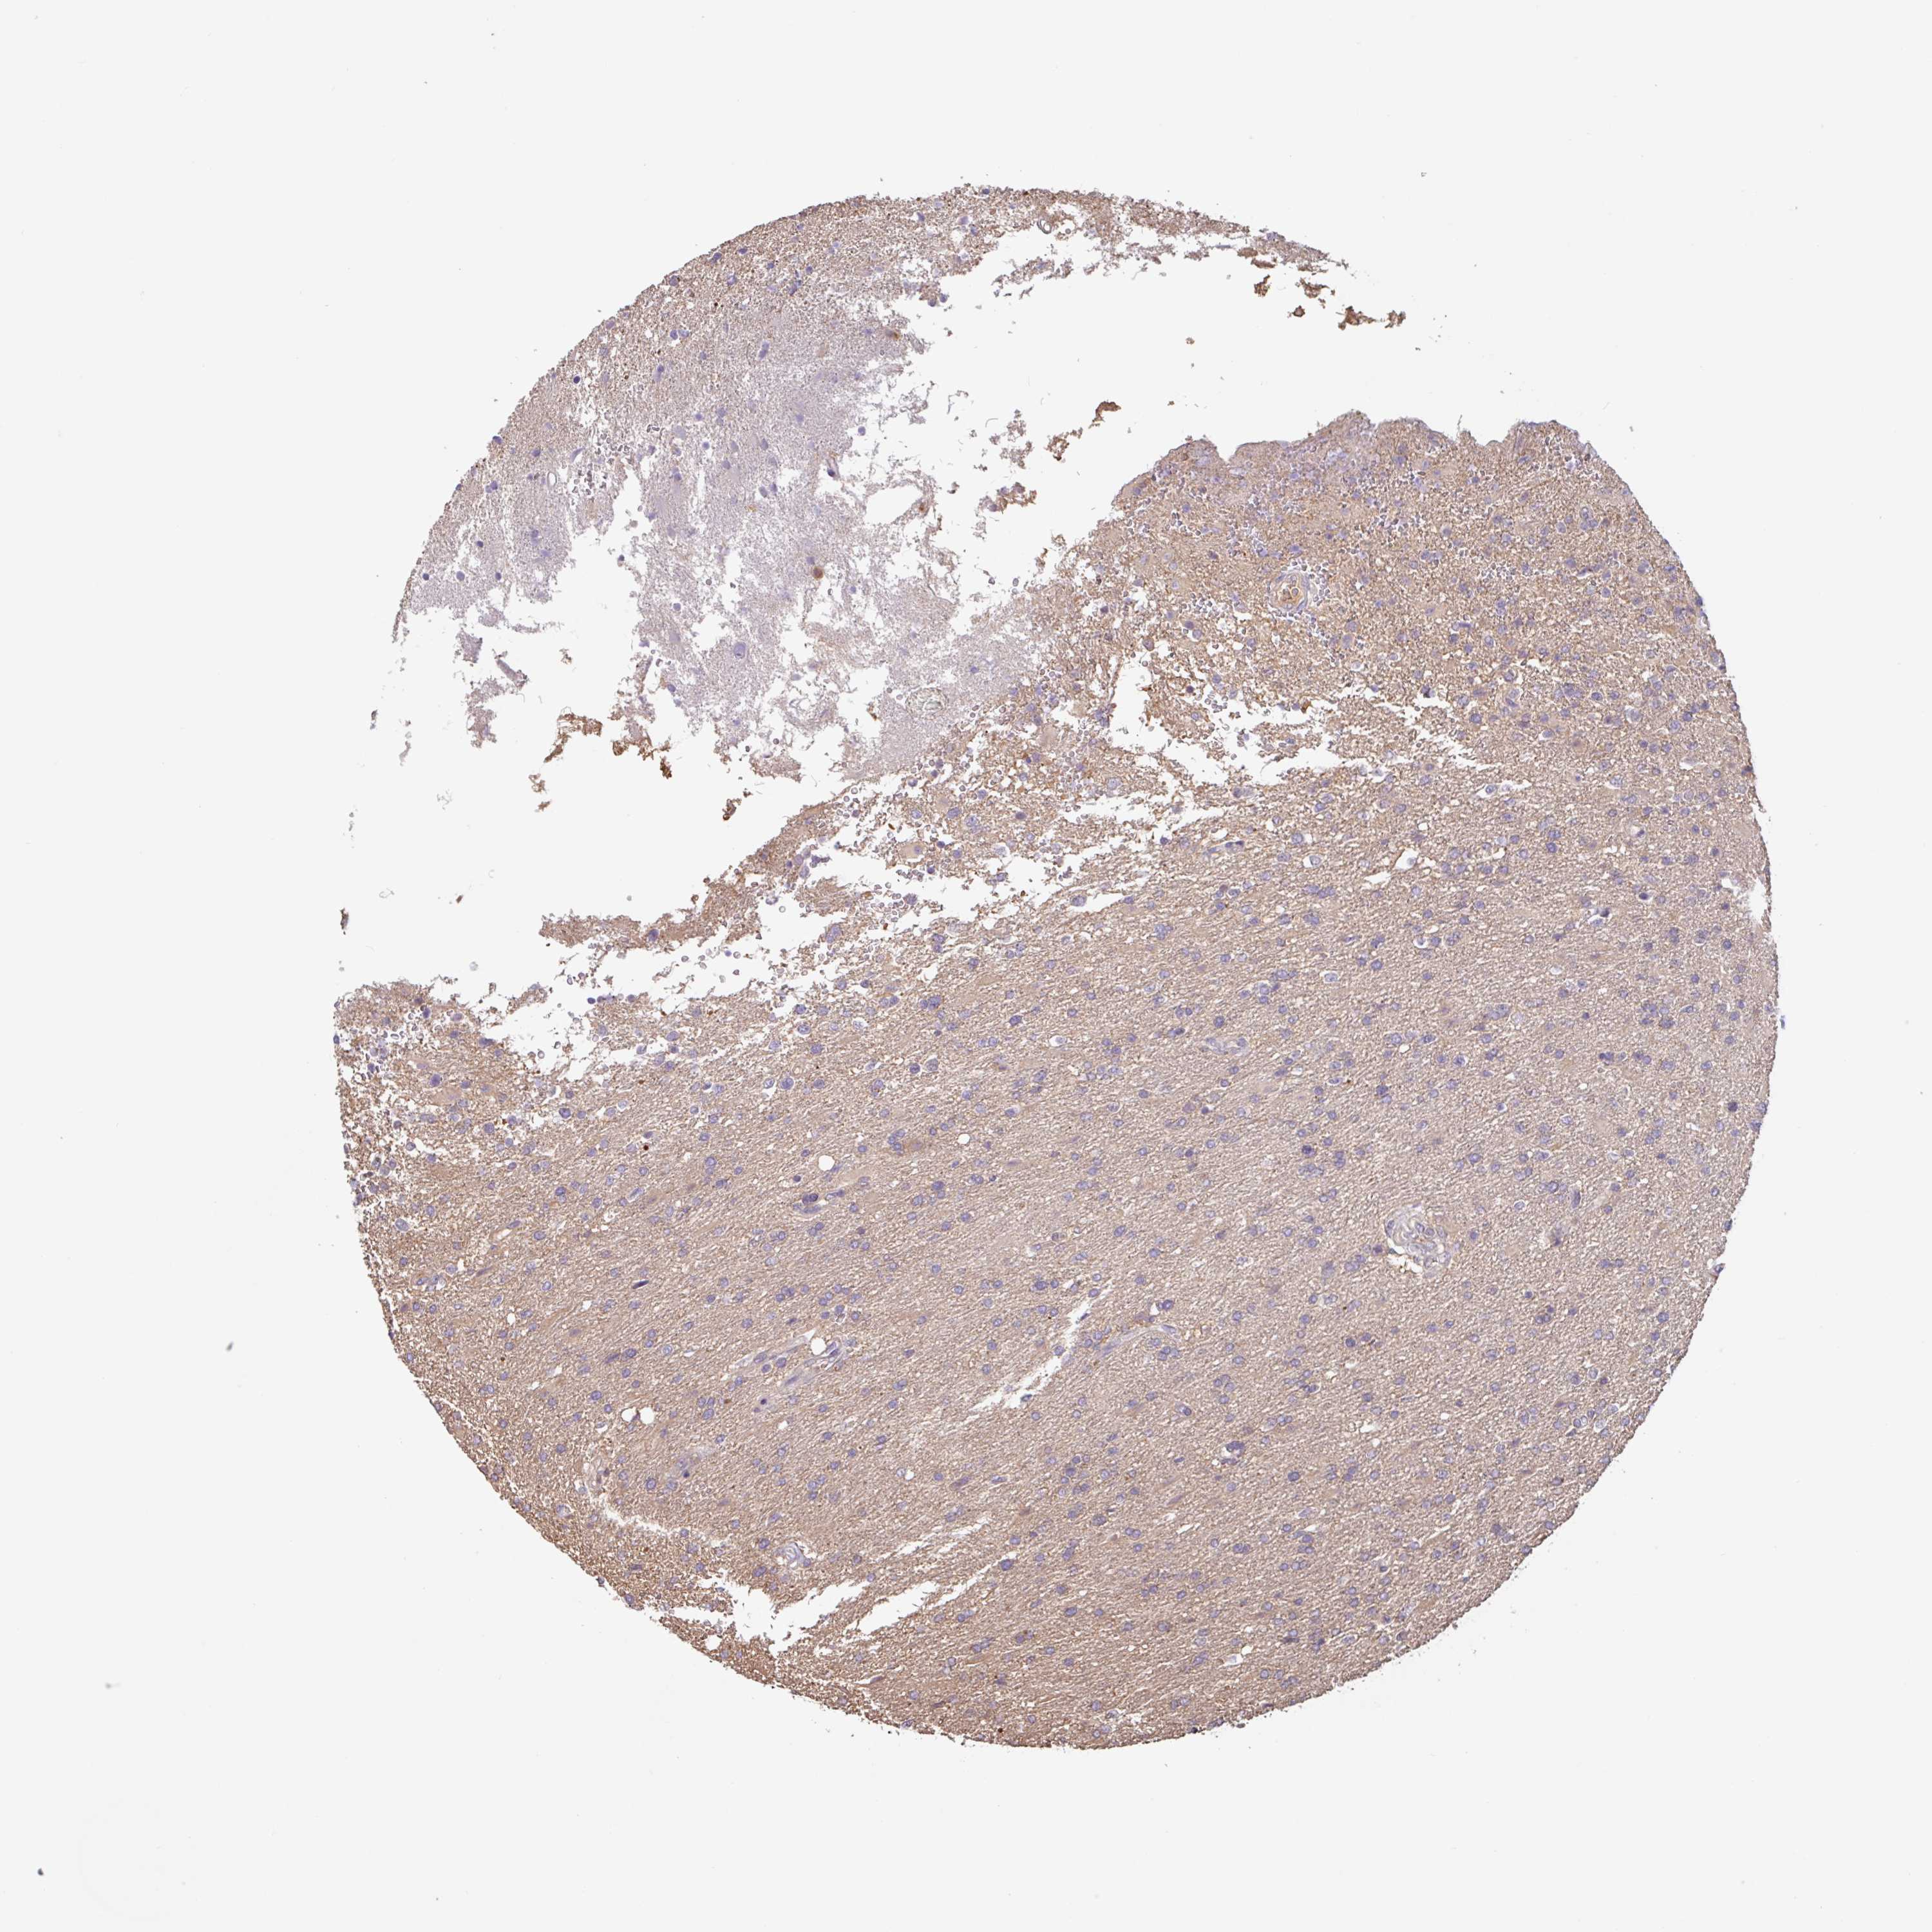

GLIOMA - Protein expressioni

A mouse-over function shows sample information and annotation data. Click on an image to view it in a full screen mode. Samples can be filtered based on level of antibody staining by selecting one or several of the following categories: high, medium, low and not detected. The assay and annotation is described here.

Note that samples used for immunohistochemistry by the Human Protein Atlas do not correspond to samples in the TCGA dataset.

Antibody stainingi

Antibody staining in the annotated cell types in the current human tissue is reported as not detected, low, medium, or high, based on conventional immunohistochemistry profiling in selected tissues. This score is based on the combination of the staining intensity and fraction of stained cells.

Each image is clickable and will lead to virtual microscopy that enables deeper exploration of all samples and also displays staining intensity scores, fraction scores and subcellular localization as well as patient and tissue information for each sample.

Antibody HPA024524

Antibody HPA053090

Staining

High

Medium

Low

Not detected

Intensity

Strong

Moderate

Weak

Negative

Quantity

>75%

75%-25%

<25%

None

Location

Nuclear

Cytoplasmic/membranous

Cytoplasmic/membranous,nuclear

Glioma, malignant, High grade

Glioma, malignant, Low grade